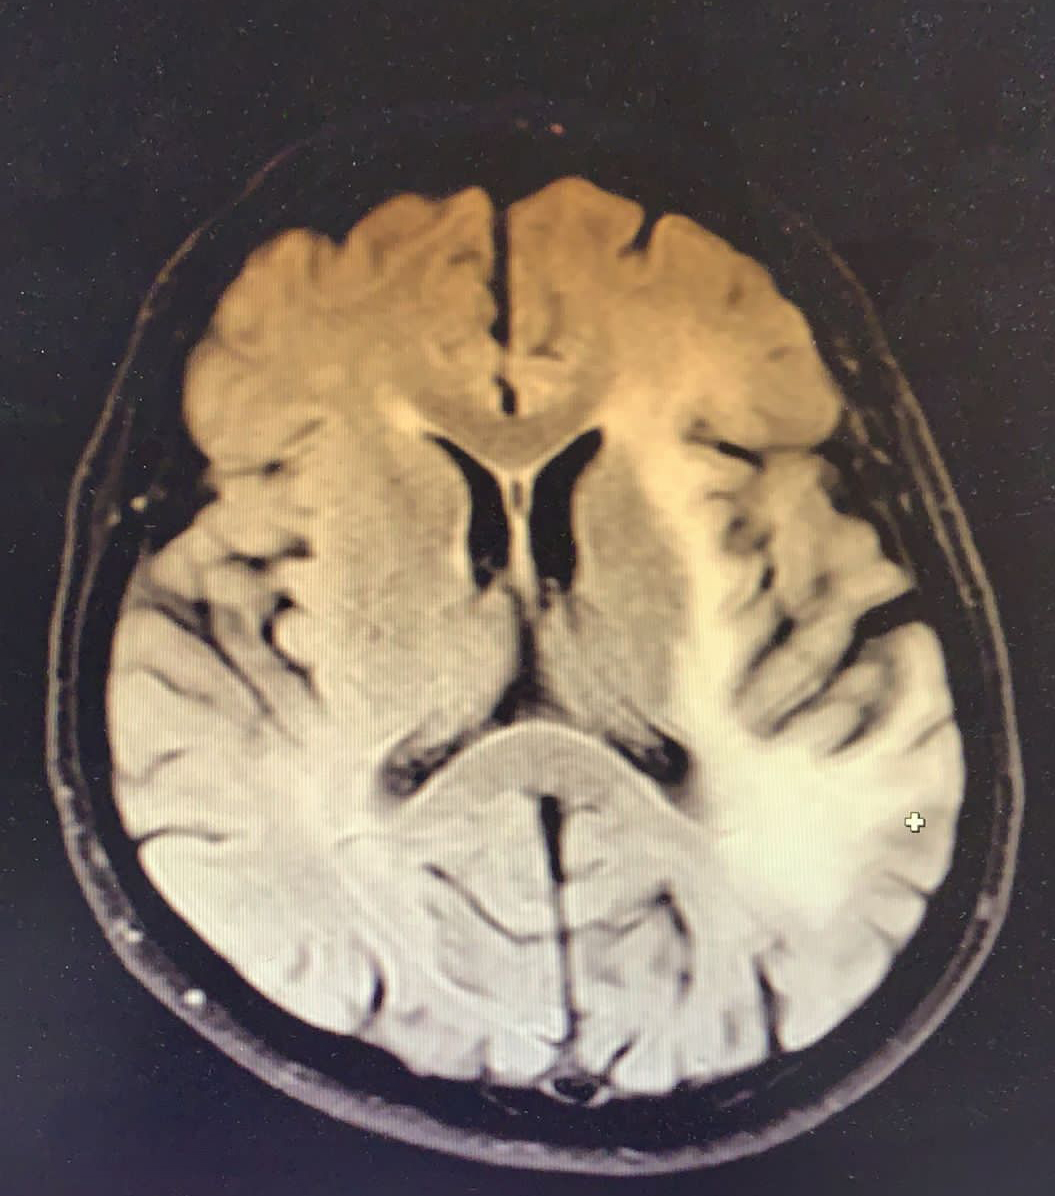

Tedavinin ikinci ayında hasta kliniğimize yaklaşık iki haftadır olan konuşma bozukluğu yakınması ile başvurdu. Fizik muayende genel durumu iyi, şuuru açık, konuşması afazikti. Basit ve tekli emirleri yerine getirebiliyordu. GKS 15 olan hastada sağ kol ve bacakta kas gücü 4/5 idi, duyu defisiti saptanmadı. Yapılan kontrastlı kranial görüntüleme bir önceki kranial MRG tetkiki ile kıyaslandığında eski tetkikte lezyonun insular korteksle sınırlı olduğu güncel incelemede ise kısa sürede belirgin progresif değişiklikler geliştiği şeklinde raporlandı (Resim 2).